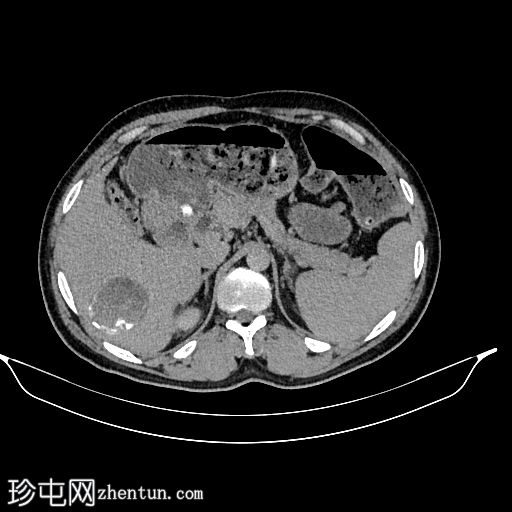

轴位

平扫

肝脏VII段可见一边界清晰的囊性病变,内部有分隔,囊壁可见钙化。

右肾中央部分(肾门)可见一囊性病变,中心可见基质,周围可见子囊。该病变与肾盂肾盏无交通。病变周围可见两处高密度影,位于上、中肾盏,无法区分是结石还是病变壁钙化。另可见上极肾盏中度扩张。